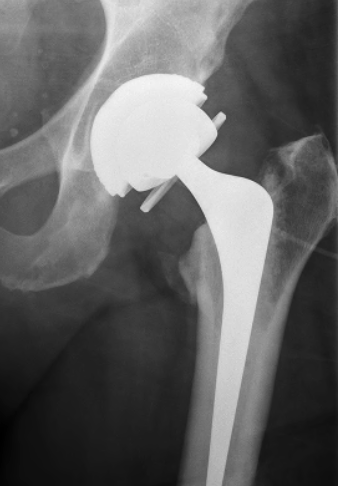

Dual mobility

van Eecke et al Hip Pelvis 2020

- systematic review of constrained and dual mobility in revision THA

- 46 studies and 5,600 hips

- survival: DM 94.7% vs. constrained 81.0%)

- dislocation rates: DM 2.6% vs. constrained 11.0%

- acetabular loosening rates: DM 1.0% vs. constrained 2.0%